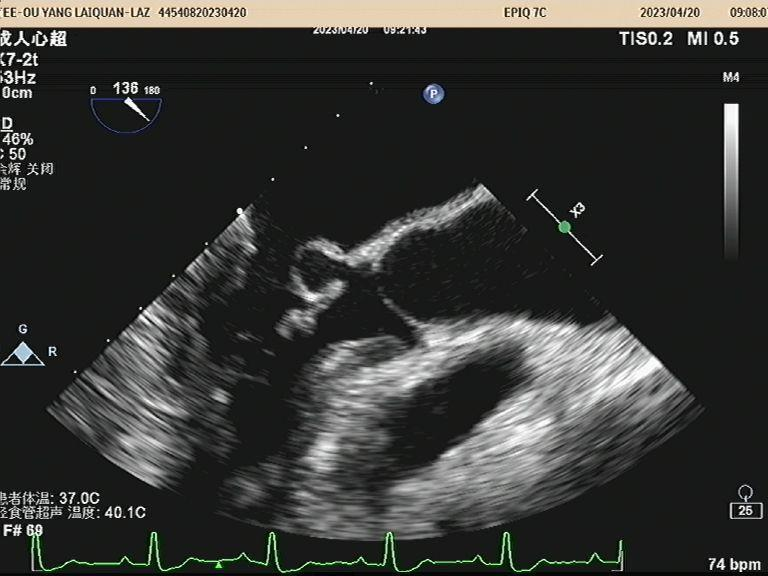

经食管超声心动图是将超声探头置于食道或胃内,紧邻心脏后部结构探测血管、心脏形态结构及功能改变的一种超声显像方法,图像清晰,尤其对心脏后部结构、左心耳血栓等独具优势,近日,我院功能科成功实施首例经食管超声心动图检查,实现了更近距离“看心”,标志着我院心脏超声检查水平迈上了一个新台阶。

(图为高洪波主任带领团队开展经食道超声心动图检查)

高洪波介绍,经食管超声心动图(TEE)是将超声探头置入食管内,从心脏的后方向前近距离探查其深部结构,可以实时观察心脏的结构、形态,并对心脏血流动力学情况和心功能状态做出合理评价。该方法避免了胸壁、肺气等因素的干扰,故可显示出清晰的图像,提高对心血管疾病诊断的敏感性和可靠性,是经胸超声心动图(TTE)的有效补充。